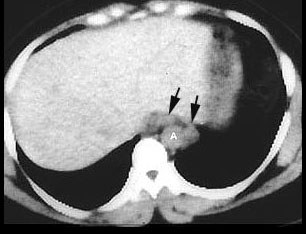

An abnormal radiograph of an asymptomatic nurse led to a CT study . CT showed these enlarged posterior mediastinal lymph nodes (arrows) next to the aorta (A). Bilateral hilar adenopathy was also shown. The posterior mediastinum is the least common site of adenopathy in sarcoidosis, but transbronchial biopsy showed nonceaseating granulomas. The nurse remains asymptomatic ten years later. |